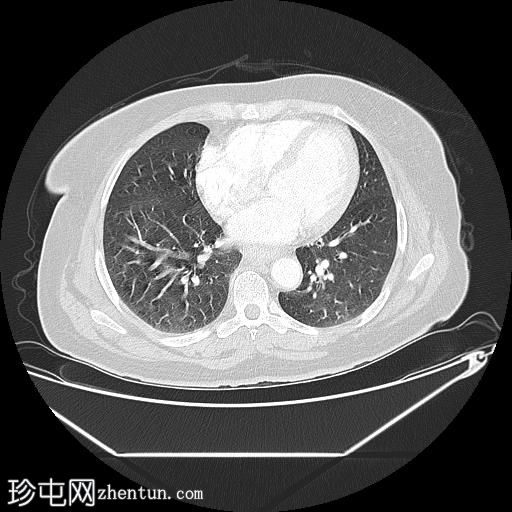

轴位(口服造影剂)

肺

中段食管壁增厚,提示

肿瘤

浸润,长约10厘米。肿块与左主支气管后壁及降主动脉紧密接触。未见侵犯邻近结构的迹象,也未触及区域淋巴结肿大。